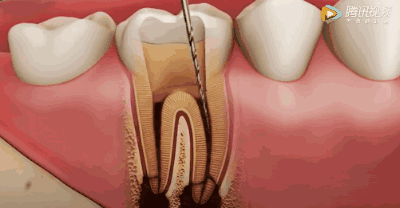

用根管器械在牙髓上做活塞运动

将坏的牙髓清理干净。目的是去净根管壁上的感染物,通过根管器械的切削作用去除感染的牙本质并清理根管壁细菌以利于根管充填。